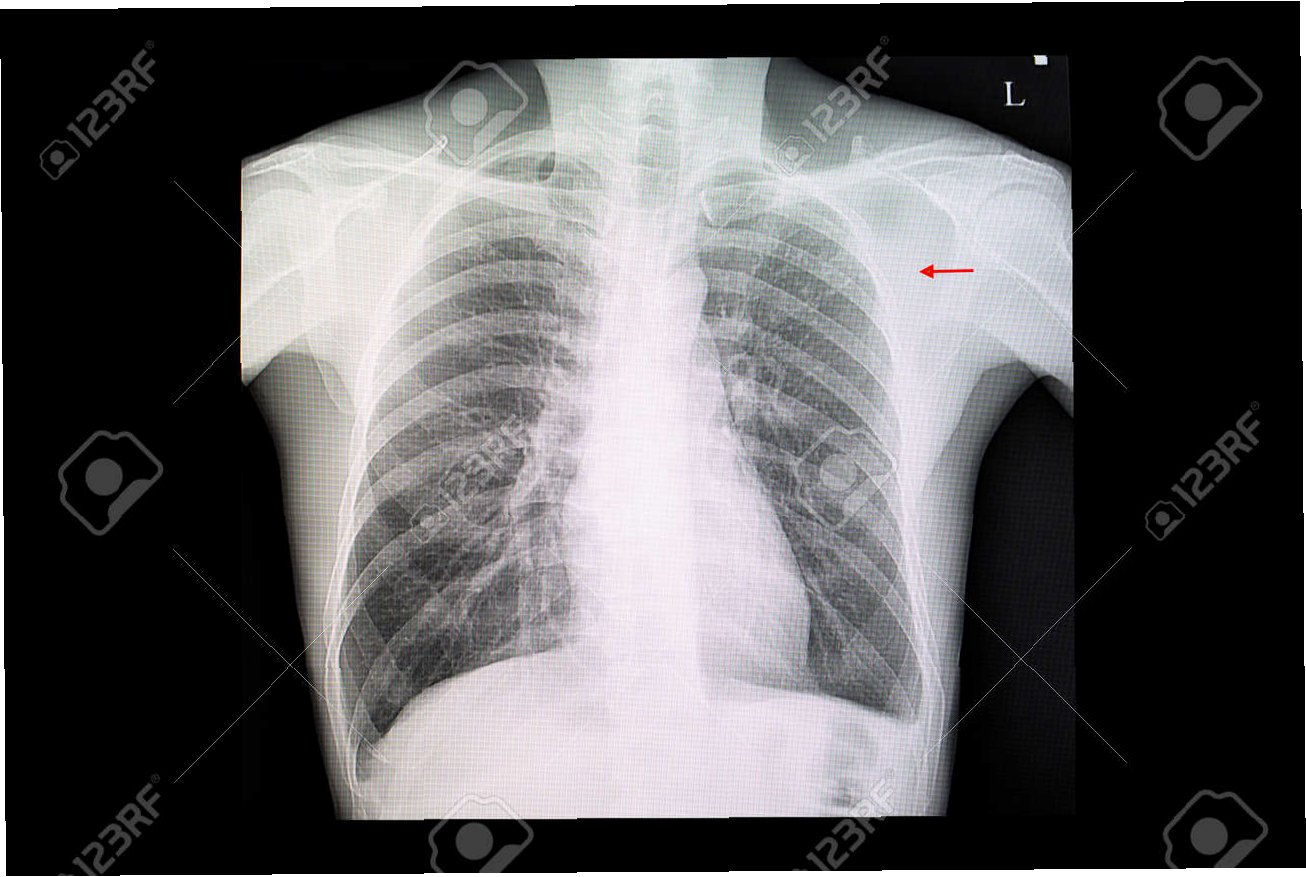

기존 유방암 검사는 딱딱한 기판에 신체를 대고 압박하여 X선을 투과시키는 방식으로 진행되었습니다. 이 과정에서 환자들은 상당한 불편함과 통증을 느껴야 했습니다. 하지만 엑스웨어 섬유는 브래지어처럼 몸에 밀착되어 압박 없이 검사가 가능합니다. 이는 환자들의 심리적 부담을 줄이고, 검사 과정의 편안함을 높여줍니다. 엑스웨어 섬유는 딱딱한 감광 소자를 사용하는 기존 방식의 단점을 극복하고, 유연하고 부드러운 형태로 제작되어 환자 중심의 의료 서비스를 제공합니다.